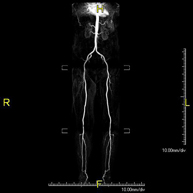

Angio RM Arterial d'extremitats inferiors

Angio RM Arterial d'extremitats inferiorsProva diagnòstica no invasiva que consisteix en l'estudi vascular del sector aorto-ilíac i dels vasos arterials de les dues extremitats inferiors, am l'obtenció d'imatges d'alta definició anatòmica mitjançant l'ús d'un camp electromagnètic i ones de ràdio (amb un emissor i un receptor). És indispensable l'ús de contrast paramagnètic (Gadolini). No obstant, no utilitza radiació ionitzant. La qualitat de les imatges permet realitzar reconstruccions en 2D i 3D. Està especialment indicat en aquells pacients en els que hi ha sospita de malaltia vascular a les dues extremitats, en pacients amb malaltia vascular de les dues extremitats com a mapa vascular abans del tractament (percutani o quirúrgic), com a mapa vascular prequirúrgic en pacients amb lesions òssies o musculars que requereixin cirurgia, etc.